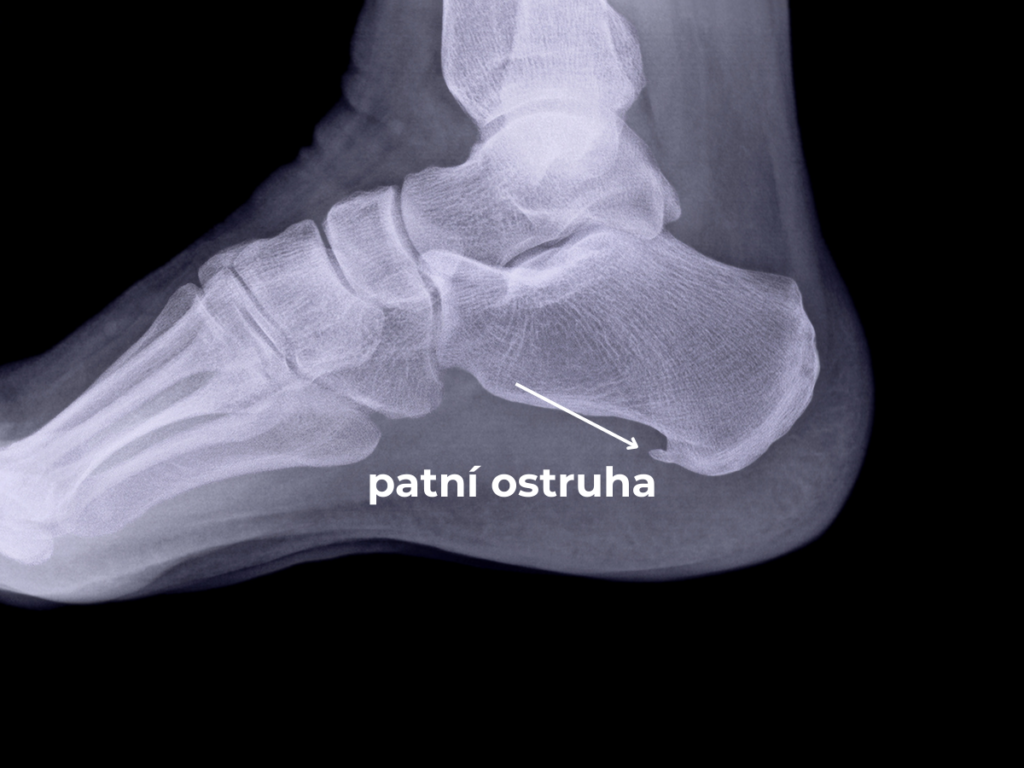

Bolí vás pata při každém došlapu, jako byste šlápli na hřebík? Trápí vás ostrá bolest chodidla, která vystřeluje až do lýtka, a ty nejhorší stavy zažíváte ráno při prvních krocích z postele nebo po delším sezení? Pak vás pravděpodobně trápí plantární fasciitida – tedy zánět plantární fascie (vazivové tkáně na plosce nohy). Tento bolestivý stav je v laické veřejnosti často chybně označován pouze jako patní ostruha, i když samotný kostěný výrůstek obvykle nebývá přímým zdrojem vašich potíží.

Mezi lidmi koluje mýtus, že bolest způsobuje ten kostěný výrůstek (ostruha). Pravda je však taková, že samotná ostruha nebolí. To, co způsobuje nesnesitelnou bolest, je zánět okolní měkké tkáně – plantární fascie. Ostruha je pouze důsledkem dlouhodobého, neřešeného přetížení a zánětu, kdy si tělo v místě úponu začne vytvářet kalcifikaci.